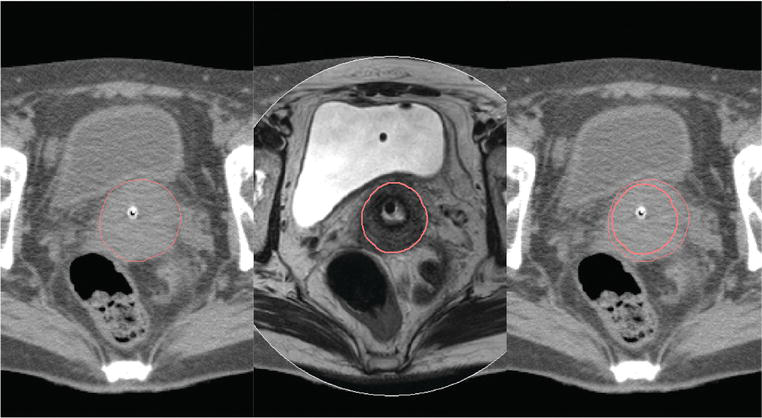

يعد علاج سرطان عنق الرحم أكثر دقة باستخدام المعالجة الكثبية تحت التصوير المقطعي المحوسب والتصوير بالرنين المغناطيسي، لأنه يستهدف الورم مع تجنيب الأنسجة السليمة.